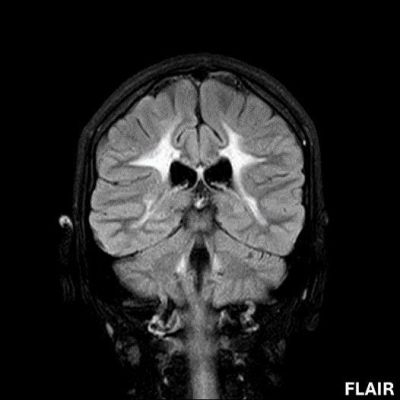

- A) Aksiyel T2A ve koronal T2A sekanslarda sentrum semiovale, korona radiata ve bazal ganglionlar düzeyinde bilateral frontoparietal derin periventriküler beyaz cevherde birleşme eğilimi gösteren hiperintens gliotik sinyal değişiklikleri (oklar) ve aksiyel T2A serilerde servikal spinal kordda posterior kolonda, lateral kesimlerde sinyal artımları (oklar) izlendi.

- LBSL, karakteristik radyolojik özelliklere sahiptir. MRG’de tipik olarak bilateral ve simetrik beyaz cevher sinyal değişiklikleri görülürken, subkortikal U lifleri, internal kapsülün posterior kolları, trigeminal sinir traktları, serebellum, korpus kallozumun spleniumu, medulla oblongata ve omurilikteki dorsal kolonlar ile lateral kortikospinal traktlar genellikle korunur.

- Etkilenen bölgelerde T1’de hipointens, T2/FLAIR’da hiperintens sinyal değişiklikleri izlenir. DWI’de lezyonların periferinde kısıtlı difüzyon görülebilir. MRS’de beyaz cevherde laktat artışı saptanabilir, ancak bu her hastada mevcut değildir.

- LBSL tanısında majör kriterler; subkortikal U lifleri korunmuş serebral beyaz cevher, servikal düzey dahil omurilik dorsal kolonları ve lateral kortikospinal traktlar, medulla oblongata piramitleri veya medial lemniskus dekusasyonu tutulumu iken; minör kriterler korpus kallozum spleniumu, internal kapsül posterior kolu, superior ve inferior serebellar pedinküller, trigeminal sinir traktları, mezensefalik trigeminal yollar, medulla oblongata anterior spinosebellar traktları ve serebellar beyaz cevherdeki sinyal değişiklikleridir.